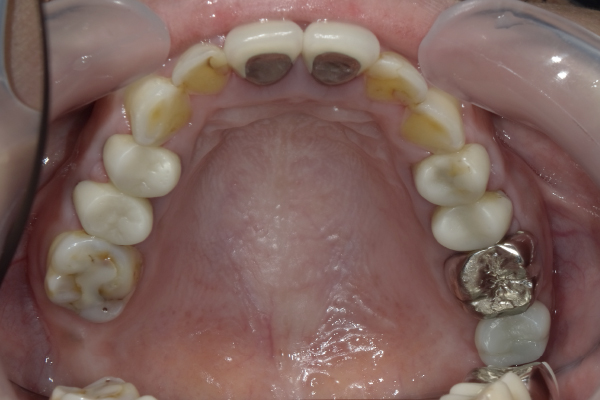

Case12

| 主訴 | 左右の歯が無い所にインプラントして欲しい |

|---|---|

| 治療期間 | 約3か月 |

| 治療費 | 1,050,000円 |

| 治療内容 | 左右の奥歯が無かったので、患者様と相談し、右上にはノンクラスプデンチャー(バネが見えない入れ歯)、左側にはインプラントを2本入れ、ブリッジという構造で上物を3本分入りました。今までとは全く食べれるものが変わって大変喜んでおられました。 |

| 治療の リスク | インプラントも残っている歯と同様に歯周病になる可能性がある |